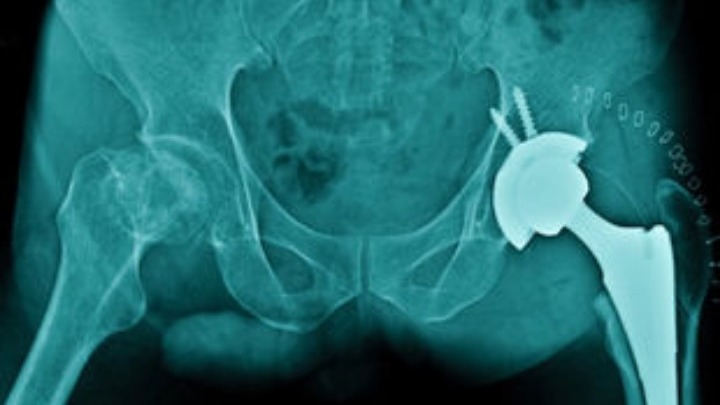

Οκτώ

στις δέκα επεμβάσεις αντικατάστασης γόνατου και έξι στις δέκα

αντίστοιχες επεμβάσεις ισχίου, γνωστές και ως ολικές αρθροπλαστικές,

αντέχουν έως 25 χρόνια, ενώ οι εννέα στις δέκα διαρκούν τουλάχιστον για

15 χρόνια, σύμφωνα με μια νέα διεθνή επιστημονική έρευνα.

Έως

σήμερα υπήρχαν πολύ λίγα στοιχεία για το πόσο πετυχημένες είναι αυτές

οι χειρουργικές επεμβάσεις στο ισχίο και στο γόνατο, οι οποίες

αντικαθιστούν την δυσλειτουργική άρθρωση (συνήθως λόγω οστεροαρθρίτιδας)

με μια τεχνητή άρθρωση. Η νέα μελέτη, που ανέλυσε στοιχεία για περίπου

500.000 ανθρώπους σε έξι χώρες και σε βάθος 25ετίας, δείχνει ότι οι

ολικές αρθροπλαστικές έχουν μεγαλύτερη αντοχή του αναμενομένου.